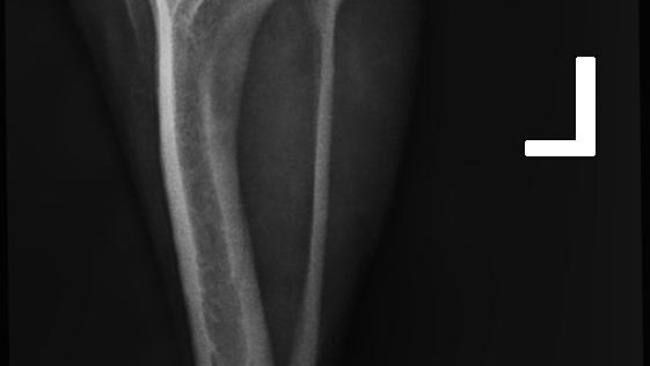

Gomez ma już za sobą dwie poważne operacje — dzielnie zniósł wszystko, mimo trudnych chwil i wielu ograniczeń. Każdy dzień to walka o jego sprawność, komfort i powrót do normalności.

Od poniedziałku zaczynamy rehabilitację, która będzie kluczowa w jego dalszym leczeniu. Przed nami długa droga, pełna wyzwań, ale też nadziei.